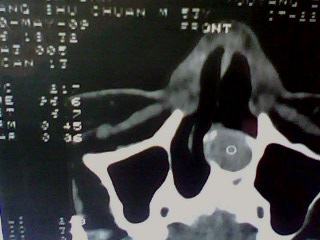

以下是引用随光逐影在2009-5-20 19:22:00的发言:[br]1)考虑左上颌骨近中线区含牙囊肿。2)鼻中隔右突偏曲。3)双侧下鼻甲肥大。